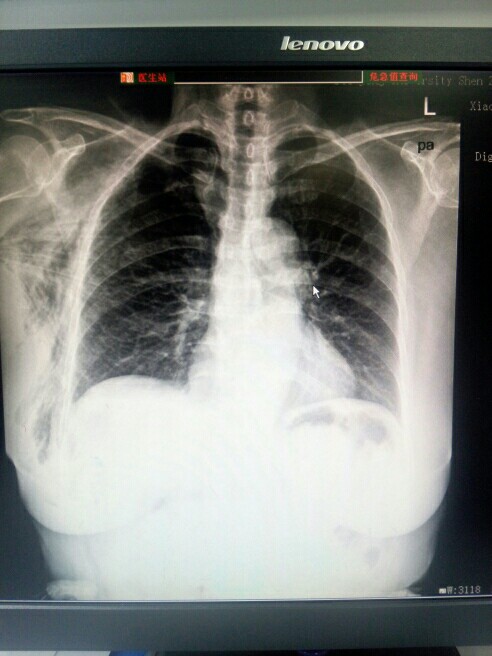

气胸

( pneumothorax )

气胸,还有什么问题,大家看出来没?